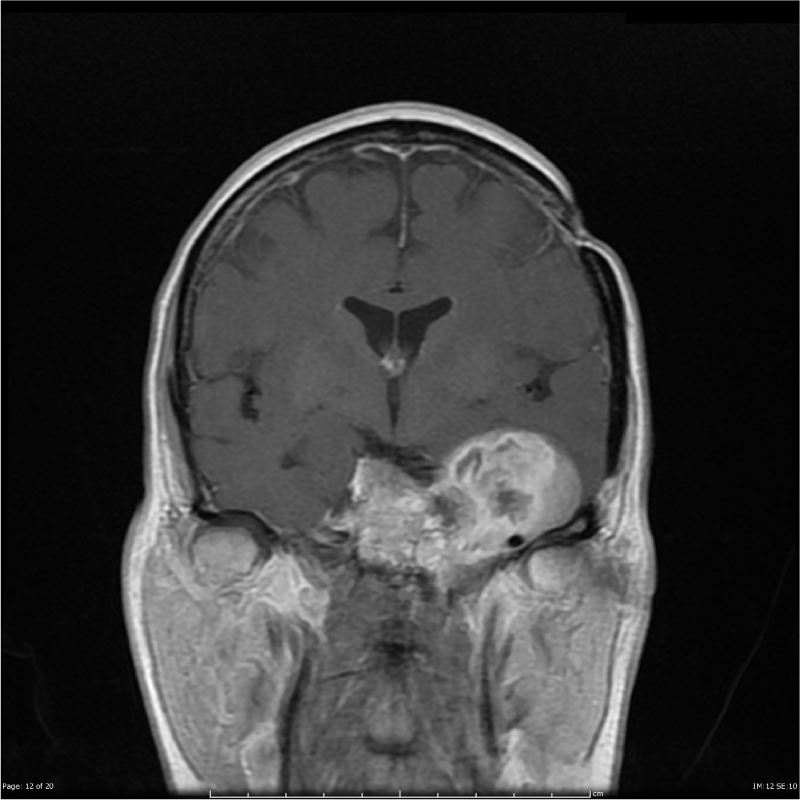

顱腦腫瘤:斜坡脊索瘤的外科治療

脊索瘤生長緩慢,但是由于具有局部侵襲,再生長的傾向可以表現(xiàn)出惡性腫瘤的特性...